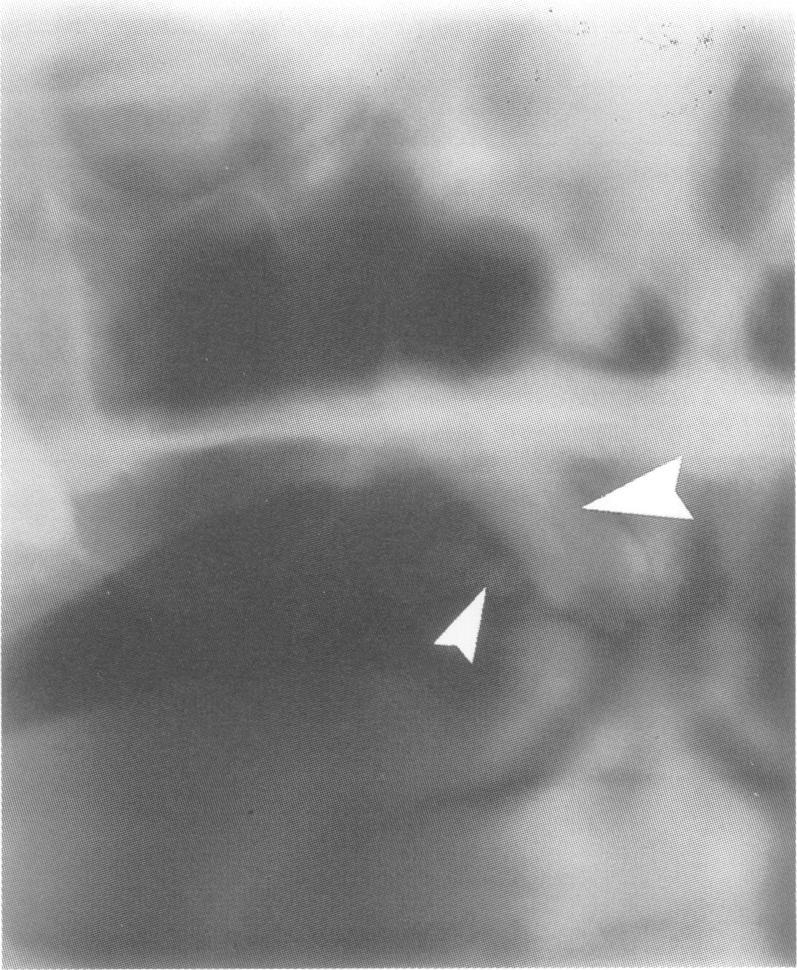

家族性腺瘤性息肉病的牙齿表型:用于牙科全景X线片变化的加权评分系统的诊断应用

The dental phenotype in familial adenomatous polyposis: diagnostic application of a weighted scoring system for changes on dental panoramic radiographs.

A weighted scoring system (Dental Panoramic Radiograph Score) taking into consideration the nature, extent, and site of osseous and dental changes on dental panoramic radiographs in familial adenomatous polyposis is described. The weighting takes into consideration the incidence of the anomaly in the general population. The reliability of the system was tested by application to 85 people known to be affected by clinical or mutation analysis, 30 people lacking mutation in the adenomatous polyposis gene, and 19 people shown to be at low risk (< 1%) by linkage analysis. Using the highest thresholds, a specificity of 100% and sensitivity of approximately 68% was obtained. If all positive findings were considered as significant, sensitivity was increased to approximately 82% but the specificity was reduced to approximately 88%. Significant DPRS findings were observed at a significantly higher frequency in patients aged over 20 compared to the patients aged 20 and under. Overall, approximately 68% of the affected subjects had significant changes, and approximately 18% had normal appearance on DPR, with the remainder having changes classified as minimal or equivocal.

摘要

本文描述了一种加权评分系统(牙科全景X线片评分),该系统考虑了家族性腺瘤性息肉病患者牙科全景X线片中骨与牙齿变化的性质、范围及部位。加权过程考虑了该异常在普通人群中的发生率。通过将该系统应用于85名经临床或突变分析确诊患病的患者、30名腺瘤性息肉病基因突变阴性者以及19名经连锁分析显示低风险(<1%)者,对该系统的可靠性进行了测试。采用最高阈值时,特异性为100%,敏感性约为68%。若将所有阳性结果均视为有意义,则敏感性提高至约82%,但特异性降至约88%。与20岁及以下患者相比,20岁以上患者中观察到显著牙科全景X线片评分结果的频率显著更高。总体而言,约68%的患病受试者有显著变化,约18%的受试者牙科全景X线片表现正常,其余受试者的变化分类为轻微或不明确。